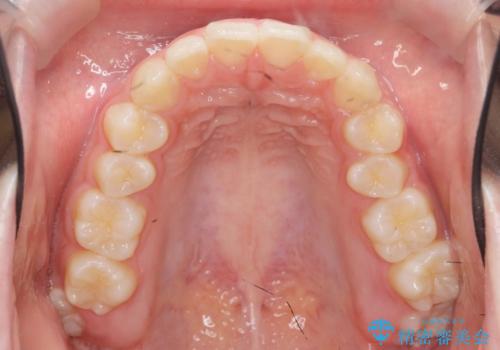

矯正治療を途中でやめてしまった、途中からの治療希望

- 他院での矯正治療中に行かなくなってしまい、装置をつけたまま矯正治療の続きを希望され来院されました。

マウスピースでは並べることが難しい左下の奥歯を部分ワイヤー矯正で並べたのち、マウスピース矯正装置インビザラインで歯並びを整えていきます。